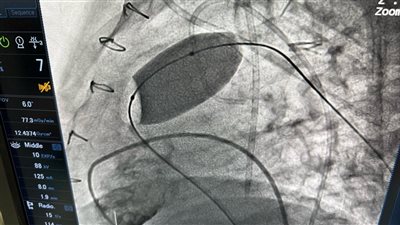

نجاح عملية دقيقة لتغيير الصمام الرئوي بالقسطرة في أكاديمية قلب المبرة

الصحة تُعلن تدشين مشروع زرع الصمام الرئوي عن طريق القسطرة بمعهد القلب